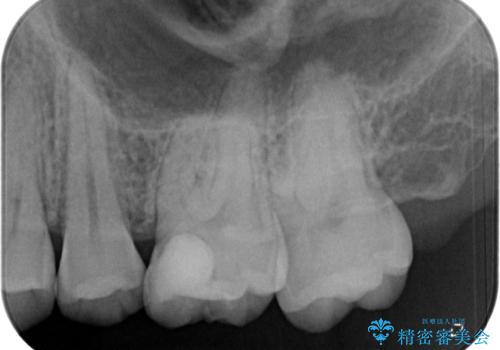

歯に穴が開いた セラミックインレー修復

- 当院でインビザラインによる矯正治療が終わった患者様です。

矯正治療終了時歯に穴が開いたとのことで、治療を希望されました。

拡大鏡視野化にて、虫歯を除去し、セラミックインレー(セラミックの詰め物)に適した形に整えました。

セラミックインレー装着時には、ラバーダム防湿にて装着をしています。